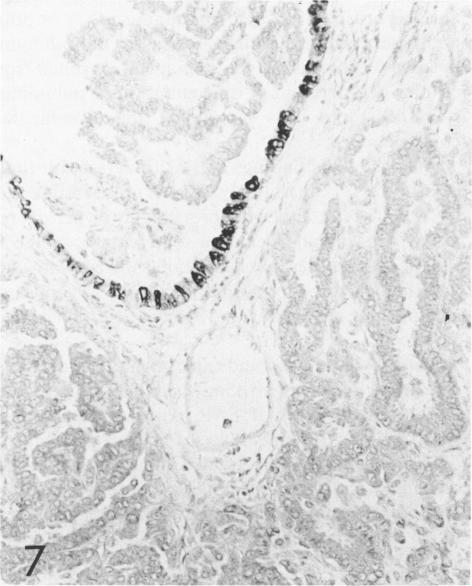

The localization of surfactant apoprotein (SAP) and the Clara cell antigen(s) (CCA) was studied in naturally occurring and experimentally induced pulmonary hyperplasias and neoplasms by avidin-biotin peroxidase complex (ABC) immunocytochemistry. Lungs of B6C3F1 and A strain mice with naturally occurring lesions, B6C3F1 mice given injections of N-nitrosodiethylamine (DEN), BALB/c nu/nu or nu/+ mice exposed transplacentally on Day 16 of gestation to ethylnitrosourea (ENU), or BALB/c nu/+ mice exposed to ENU at 8-12 weeks of age were preserved in formalin or Bouin's fixative. After ABC immunocytochemistry, SAP was found in the cytoplasm of normal alveolar Type II cells; in the majority of cells in focal alveolar and solid hyperplasias originating in peribronchiolar or peripheral locations; and in solid, tubular, papillary, and mixed adenomas and carcinomas. The larger mixed-pattern neoplasms and small or large tubular neoplasms usually had the least number of cells with SAP. The majority of large papillary adenomas and carcinomas in BALB/c mice exposed to ENU and in untreated A strain mice contained SAP in the nuclei of many neoplastic cells but only in the cytoplasm of a few neoplastic cells. CCA was found in normal Clara cells of bronchi and bronchioles but not in any hyperplastic or neoplastic lesion of any mouse studied. This study provided immunocytochemical evidence that the vast majority of naturally occurring and experimentally induced pulmonary neoplasms of mice are alveolar Type II cell adenomas and carcinomas.

采用抗生物素蛋白-生物素过氧化物酶复合物(ABC)免疫细胞化学方法,研究了表面活性物质载脂蛋白(SAP)和克拉拉细胞抗原(CCA)在自然发生和实验诱导的肺增生及肿瘤中的定位。对患有自然病变的B6C3F1和A品系小鼠、注射N-亚硝基二乙胺(DEN)的B6C3F1小鼠、在妊娠第16天经胎盘暴露于乙基亚硝基脲(ENU)的BALB/c裸鼠或裸+/+小鼠,或在8-12周龄时暴露于ENU的BALB/c裸+/+小鼠的肺组织,用福尔马林或布因氏固定液保存。经过ABC免疫细胞化学检测,发现SAP存在于正常肺泡II型细胞的细胞质中;存在于起源于细支气管周围或周边部位的局灶性肺泡增生和实性增生的大多数细胞中;也存在于实性、管状、乳头状和混合性腺瘤及癌中。较大的混合型肿瘤和小或大的管状肿瘤中通常含SAP的细胞数量最少。在暴露于ENU的BALB/c小鼠和未经处理的A品系小鼠中的大多数大乳头状腺瘤和癌,在许多肿瘤细胞的细胞核中含有SAP,但仅在少数肿瘤细胞的细胞质中含有。在支气管和细支气管的正常克拉拉细胞中发现了CCA,但在所研究的任何小鼠的增生性或肿瘤性病变中均未发现。本研究提供了免疫细胞化学证据,表明小鼠中绝大多数自然发生和实验诱导的肺肿瘤是肺泡II型细胞腺瘤和癌。